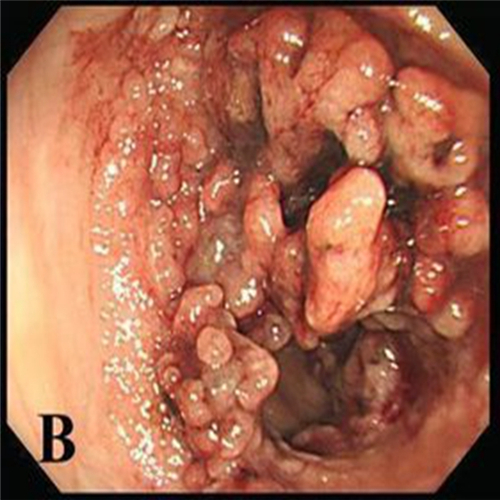

直腸息肉圖片

直腸息肉的症狀